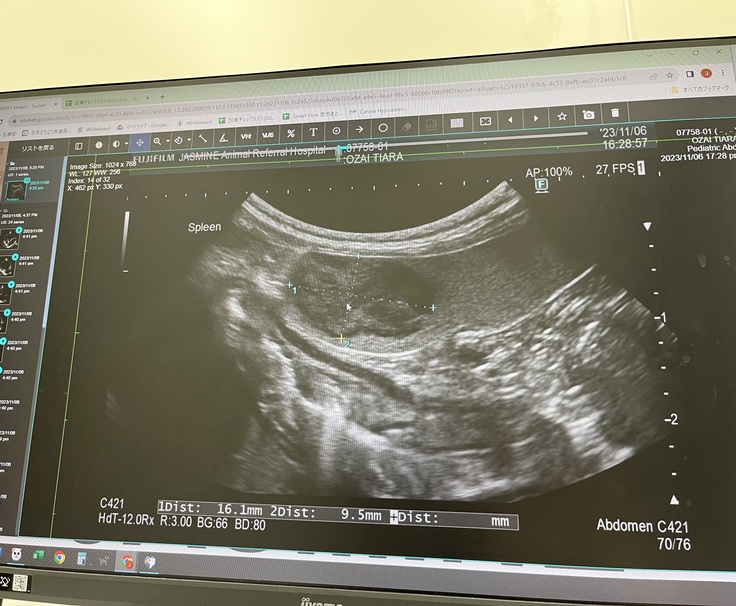

術後3ヶ月、来年の春頃には

脾臓のリンパ腫の摘出手術も控えております。